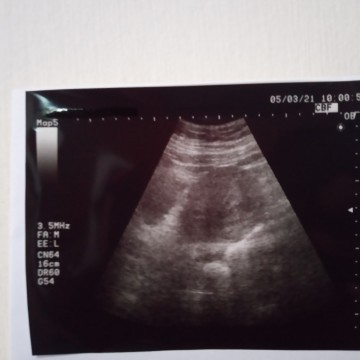

Hasil Usg belum terlihat baru terlihat rahim yang membesar

Momy2 mohon bantu jawab atau share pengalaman ya barangkali ada yg sama. Ini kehamilan saya.. HPHT saya 31 Januari 2021 harusnya 5 minggu namun saya periksa ke bidan USG baru terlihat rahim yg membesar saja. Kata bidan baru 3 minggu karena blm terlihat apa2 hanya rahim yang membesar. Hasil Testpack sudah positif garis dua bahkan 3 x saya test. Apakah ini wajar? Saya jd parno ketakutan sendiri. Mohon bantu share dan jawab ya momy2.... #seriusnanya #ingintahu #firstbaby #ingintahu